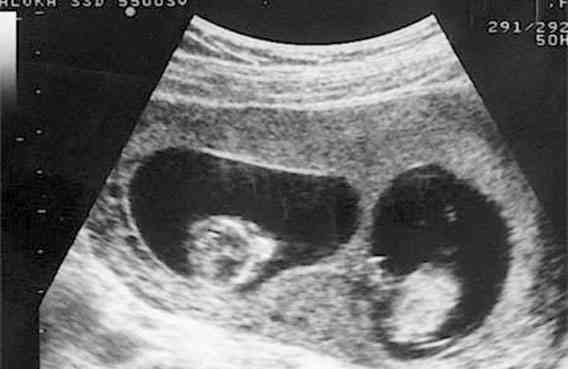

試管嬰兒移植胚胎成雙胞胎的案例還是有的,只是妊娠雙胎的風險很高,妊娠期間也會有很多併發症,如果胎兒情況不好或者是孕婦身體不理想,醫生也會建議減胎,下面可以瞭解一下移植兩個胚胎成雙胞胎的概率: